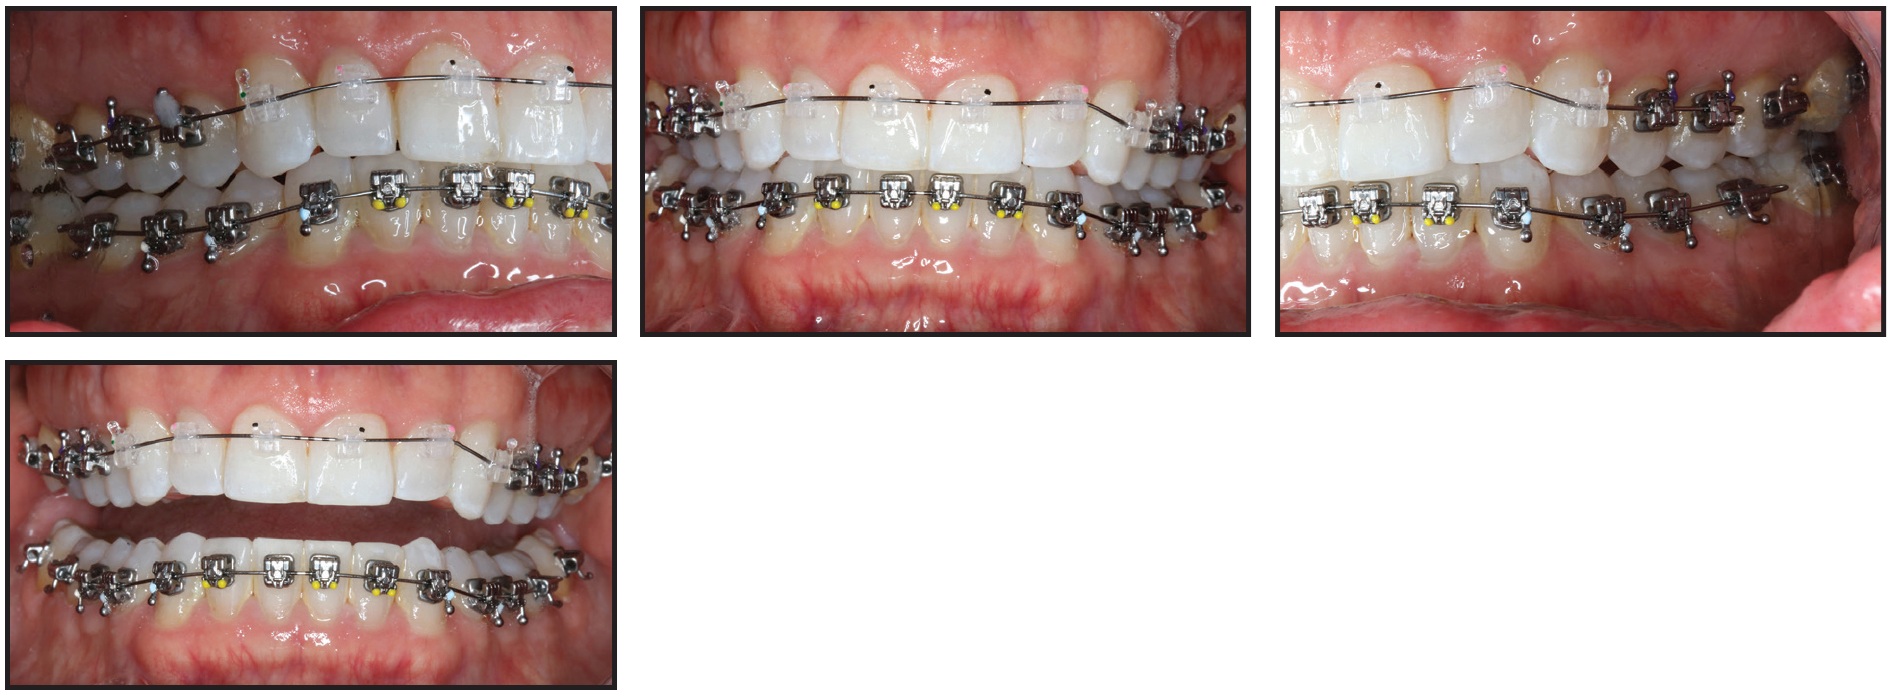

A technique known as the “Active Early” approach comprises progressive case-management strategies that complement SAP bracket positioning for early 3D control. Occlusal guides (bite turbos) and immediate light, short elastics are used from the beginning of treatment to match the lower occlusal plane with the upper. In a patient with deep overbite, this technique helps erupt the lower molars and extrude the upper anterior teeth as it moves them slightly clockwise. Case 1 demonstrates how the smile arc, enamel and gingival displays, and occlusal plane can be positively affected by SAP bracket positioning and the “Active Early” approach (Figs. 1-6).

Fig. 1 Case 1. 17-year-old female patient with disappointing result from previous 3.5 years of orthodontic treatment. (Case courtesy of Dr. Nimet Guiga, Cascais, Portugal.)

Fig. 2 Case 1. Brackets bonded with Smile Arc Protection (SAP) bracket positioning. Progressive case management strategies included inverted upper anterior brackets; posterior occlusal guides (bite turbos); and immediate light, short Class III elastics.

Fig. 3 Case 1. Smile arc developing after eight months of treatment.

Fig. 4 Case 1. Patient after 15 months of treatment, with smile exhibiting all desirable esthetic characteristics.

Fig. 5 Case 1. Comparison of pretreatment (A) and post treatment (B) photos, demonstrating improvements in smile arc, cant of upper occlusal plane, incisor and gingival display, and archform, with proper “white and pink” esthetic proportions.

Fig. 6 Case 1. Comparison of pre-treatment (A) and post-treatment (B) lateral cephalograms, showing slight clockwise rotation of maxillary occlusal plane with upper incisor extrusion in relation to stomion.